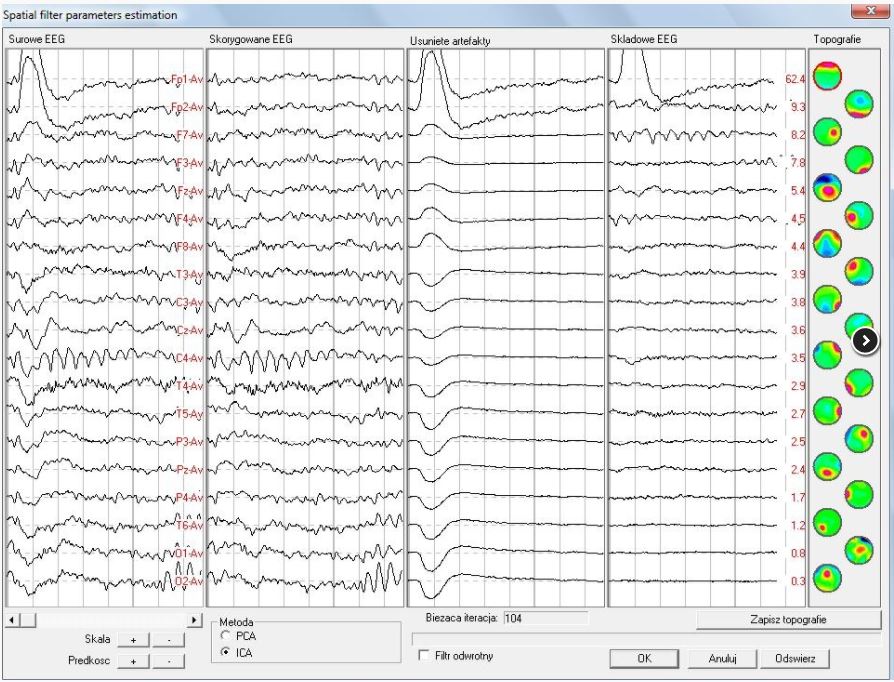

Korekcja artefaktów

Zaawansowany tryb usuwania artefaktów ułatwia i przyspiesza wyeliminowanie fragmentów ze złym zapisem EEG. Procedura korekcji artefaktów jest oparta o dekompozycję sygnału z użyciem analiz PCA lub ICA, co poprawia jakość zapisanego sygnału EEG.